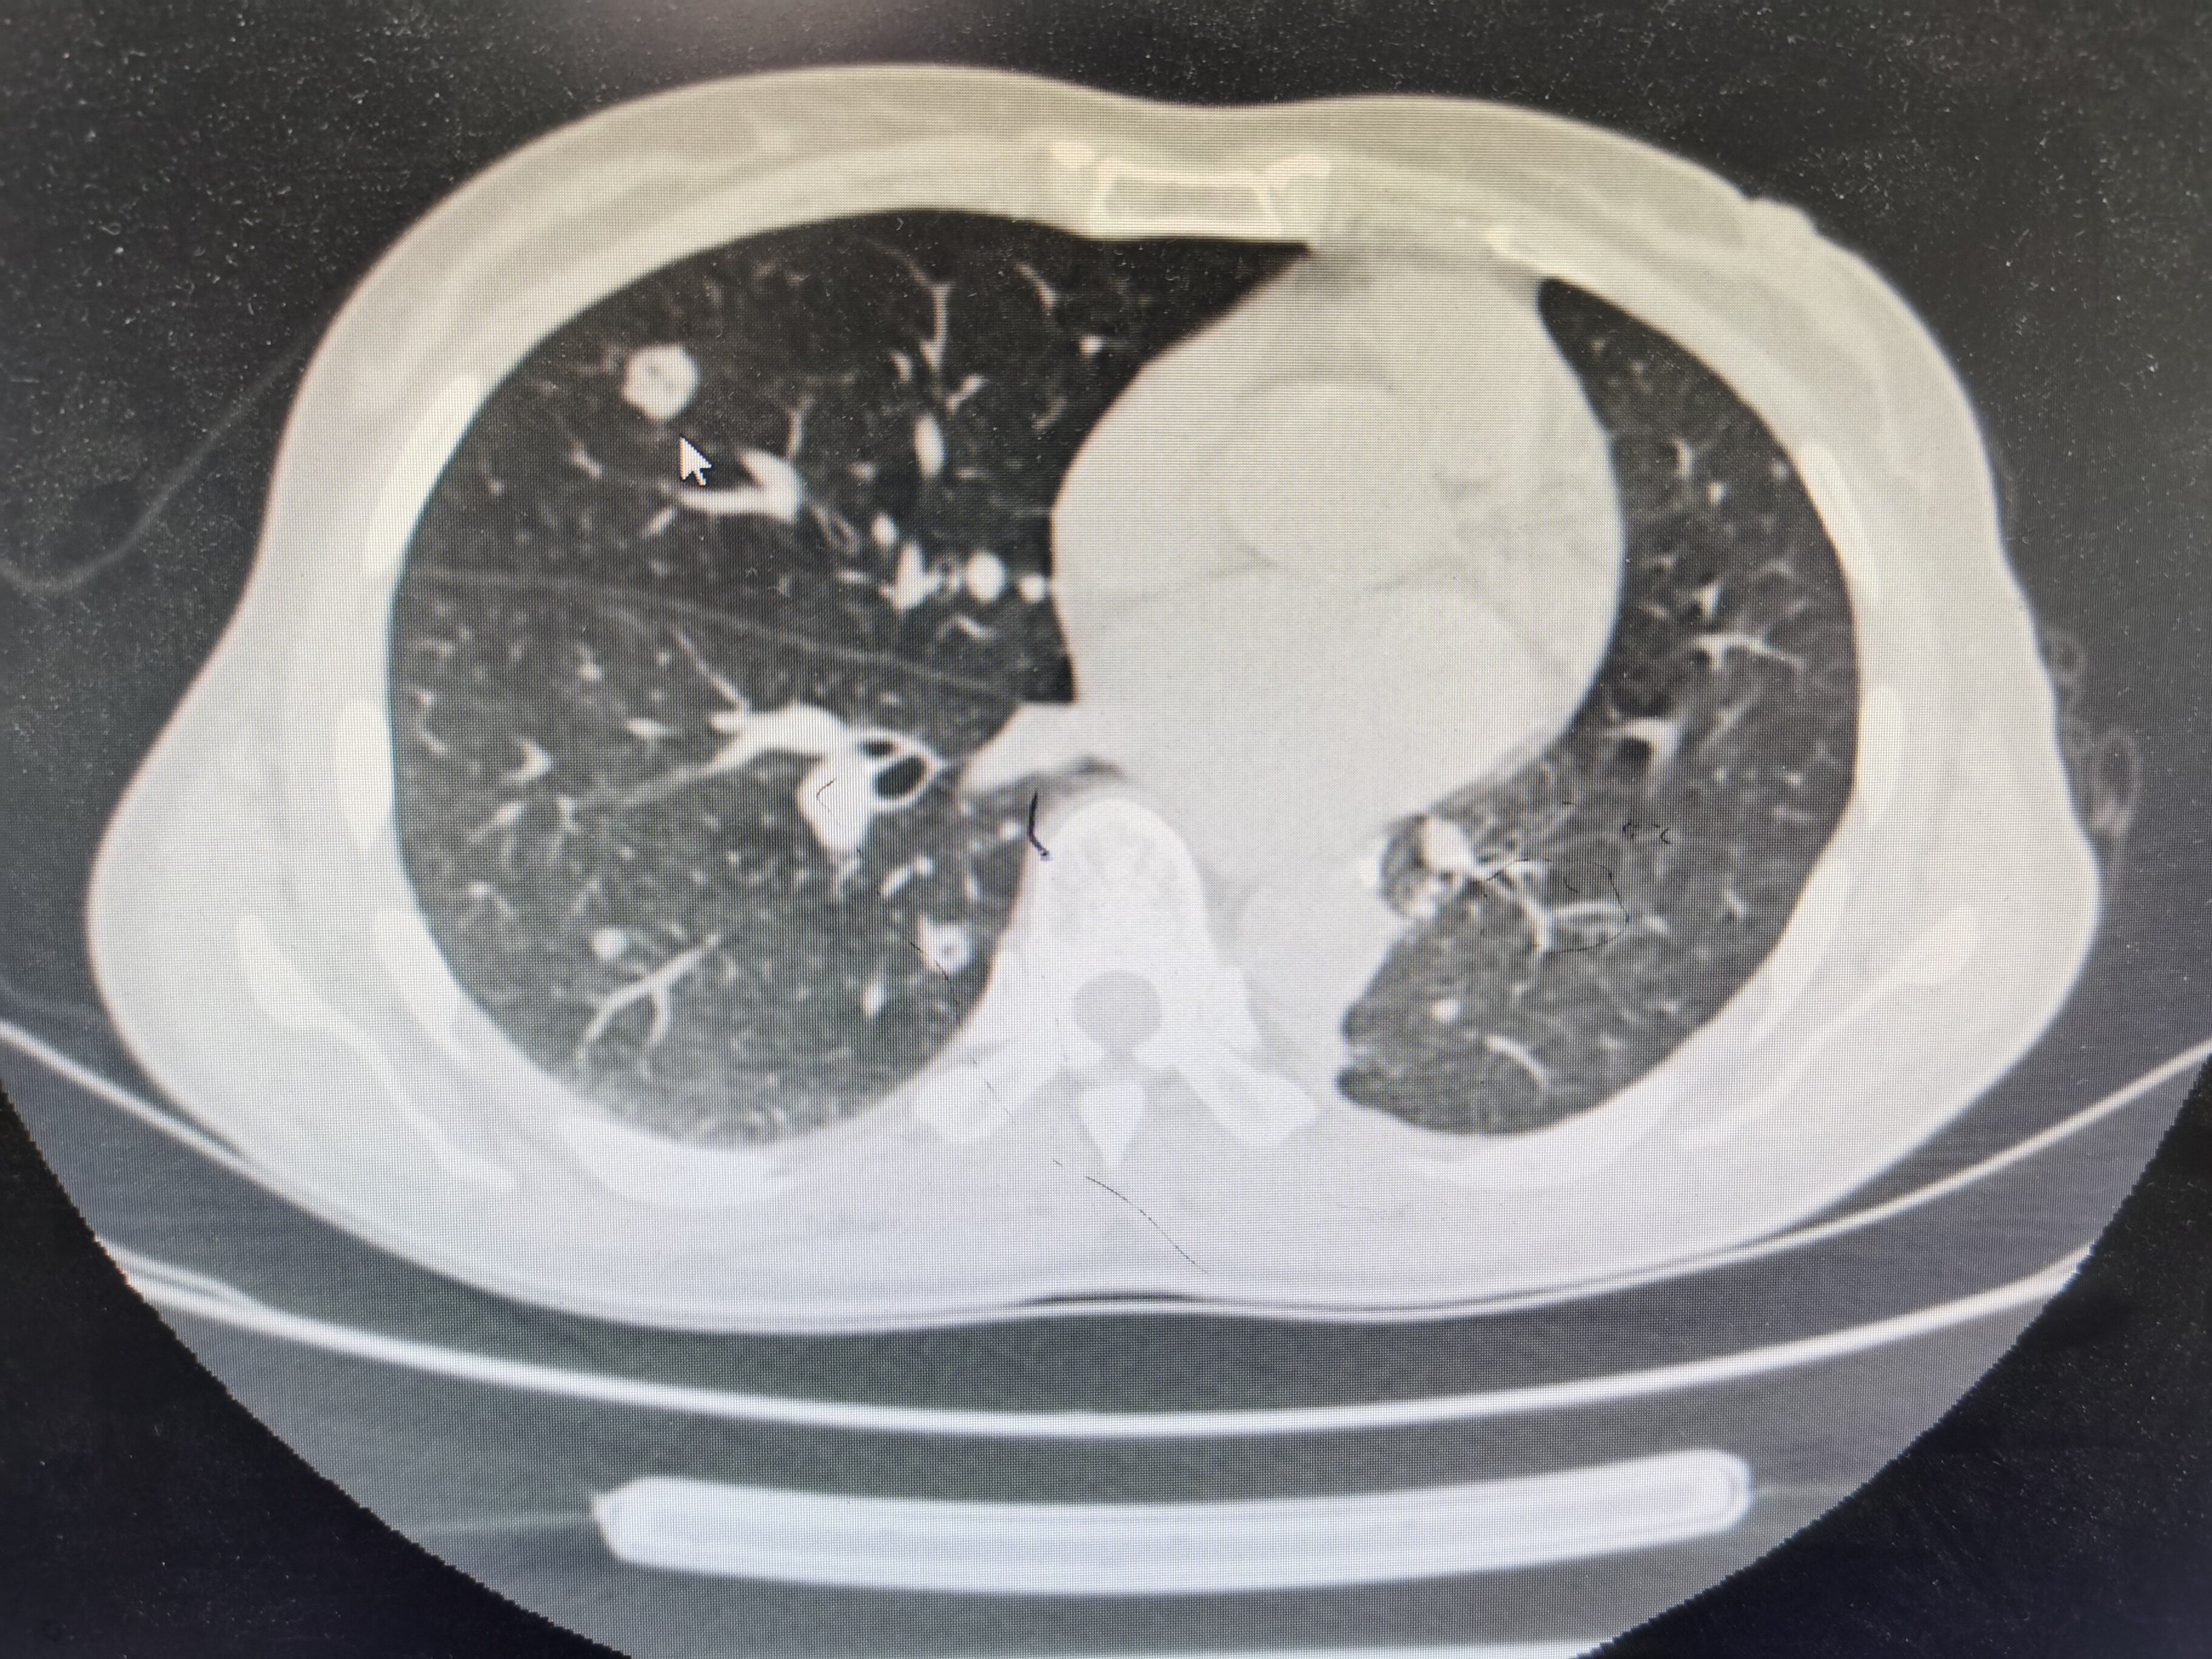

肺部恶性结节在体内的演化

图文教你看懂恶性肺结节的ct表现

直径>20mm的恶性概率达到64%~82%肺结节按照密度,可以分为"磨玻璃

查出肺结节,哪3种需要动手术?医生用ct片举例说明